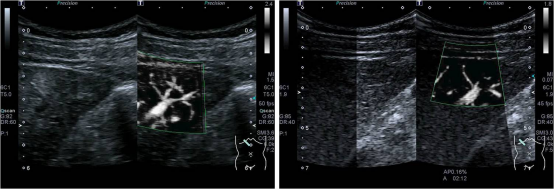

iSMI技术主要包括:

1. iSMI+Smart(Sensor)3D:操作便捷、极速成像、立体直观。

2. iSMI+VI:呈现极低速血流信号分布密度,准确检测血流信号占目标区域的像素比。

3. iSMI+CHI:SMI+超声造影,微细血管中极低流速造影微泡信号的高敏感、高分辨率成像。